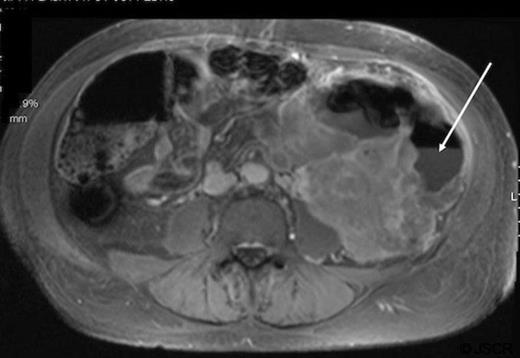

Patient B is a 61 year old male who presented with abdominal pain and weight loss. Physical exam revealed a palpable mass in the left lower quadrant. At presentation he demonstrated a leukocytosis (WBC=76 800), although he was initially afebrile and demonstrated no signs of infection. Abdominal and pelvic CT showed a mass beginning at the left kidney and attached to the sigmoid colon. A CT guided biopsy demonstrated a pleomorphic high grade sarcoma consistent with malignant fibrous histiocytoma. Further evaluation with MRI demonstrated a large, necrotic mass in the left retroperitoneum that encased the descending colon with an air-fluid level concerning for a contained colonic perforation (Figure 2). The patient was started on antibiotics and taken for surgical resection.

Abdominal MRI of patient B demonstrating an air-fluid level (arrow) of the descending colon with surrounding mass.